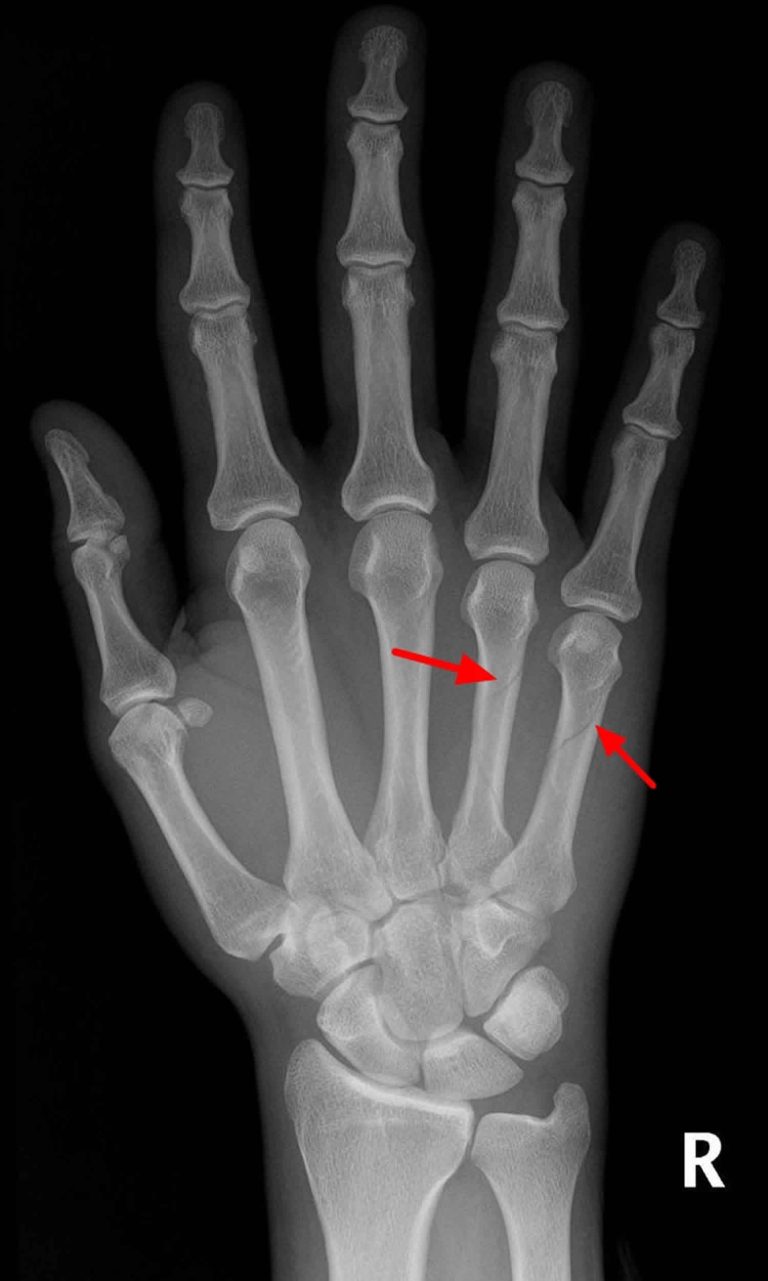

How Does a Spiral Fracture in the Hand Occur? Apricus Health What Type Of Force Would Cause A Spiral Fracture The primary cause of spiral fractures is a twisting or torsional force applied to a bone. Treatment can depend on the severity of the breakage, but may include surgery. This can occur during physical activities such as sports, falls. Torsion fracture) is a bone fracture occurring when torque (a rotating force) is applied along the axis of a bone. The. What Type Of Force Would Cause A Spiral Fracture.